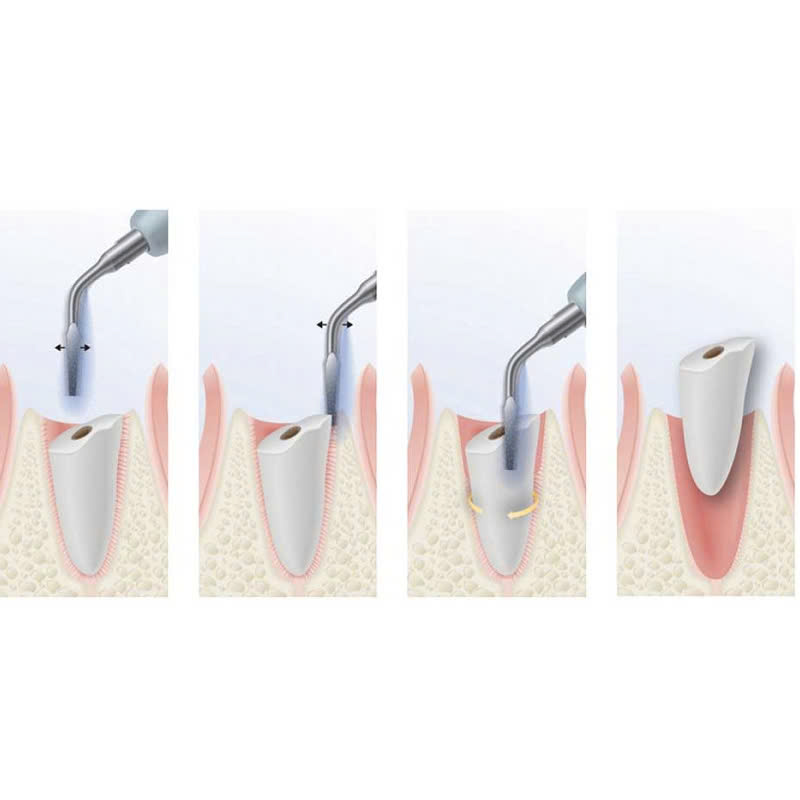

Quy trình nhổ răng bằng máy Piezotome bao gồm các bước sau:

- Khám và tư vấn: Bác sĩ sẽ thăm khám, chụp X-quang để đánh giá tình trạng răng và đưa ra phương án điều trị phù hợp cho khách hàng.

- Gây tê: Bác sĩ sẽ tiến hành gây tê tại chỗ để khách hàng không cảm thấy đau trong quá trình nhổ răng.

- Sử dụng máy Piezotome: Bác sĩ sẽ sử dụng máy Piezotome để cắt nướu và xương hàm, tách răng khỏi ổ răng một cách chính xác.

- Lấy răng ra khỏi ổ răng: Sau khi tách răng, bác sĩ sẽ nhẹ nhàng lấy răng ra khỏi ổ răng.

- Khâu vết thương: Bác sĩ sẽ khâu vết thương sau khi nhổ răng, giúp vết thương mau lành và hạn chế chảy máu.